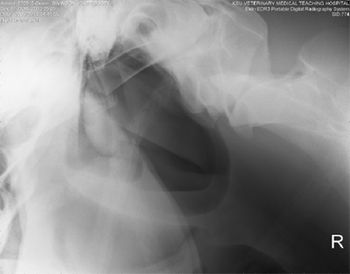

A chief concern with any trauma that causes frontal or poll injury is possible damage to the central nervous system.